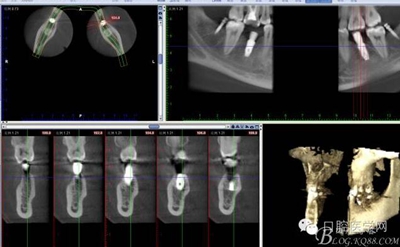

CT

因為患者要求半月內(nèi)完成,所以同期植入韓國豋騰4.5*10mm種植體